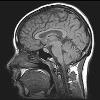

خواندن دقیق مغز توسط کامپیوتر

تجزیه و تحلیل تصاویر MRI مغز و استفاده از یک مدل ظریف ریاضی، بازسازی افکار را دقیق تر از هر زمان دیگری ممکن خواهد کرد.